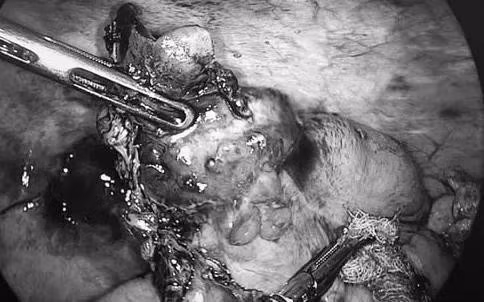

Tuy nhiên, trong quá trình phẫu thuật, ê-kíp mổ phát hiện ruột thừa có khối u bất thường, nghi ngờ tổn thương ác tính. Trước tình huống này, các bác sĩ đã hội chẩn ngay trong mổ và quyết định chuyển phương án phẫu thuật, tiến hành cắt đoạn đại tràng phải nhằm bảo đảm nguyên tắc điều trị triệt để theo chuyên khoa ung bướu.

Ca phẫu thuật được thực hiện an toàn, đúng quy trình kỹ thuật. Kết quả giải phẫu bệnh sau mổ xác định bệnh nhân mắc ung thư ruột thừa. Sau phẫu thuật, bệnh nhân hồi phục tốt, tình trạng sức khỏe ổn định và tiếp tục được theo dõi, điều trị theo phác đồ phù hợp.

Ca phẫu thuật được thực hiện an toàn/Ảnh VTV